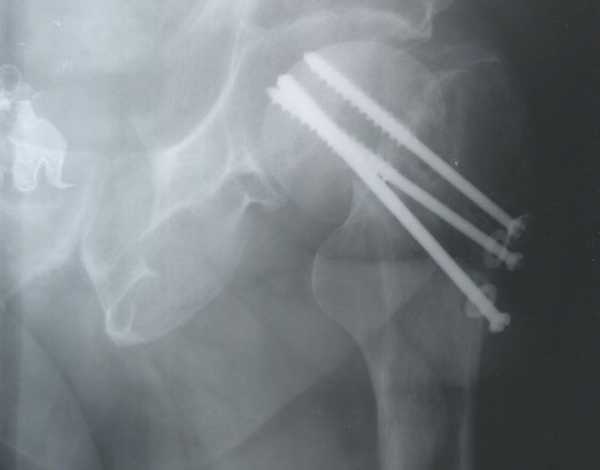

Наиболее эффективным способом лечения вколоченного перелома шейки бедра считается оперативное вмешательство, позволяющее сразу произвести репозицию отломков. В зависимости от состояния костной ткани больного может быть произведен остеосинтез – скрепление отломков кости при помощи выполненных из биологически и химически инертных материалов фиксаторов: гвоздей, винтов, спиц, штырей и пластин. При наличии у пациента остеопороза и существенных повреждениях головки и шейки бедренной кости остеосинтез может оказаться неэффективным; в таком случае выполняется эндопротезирование – полная замена тазобедренного сустава протезом.

Для его определения делается рентген в двух проекциях. Обычно такие переломы хорошо поддаются лечению. Для этого делается малоинвазивная операция: через проколы в кость вводят три винта, которыми скрепляют отломки. Далее перелом фиксируется наложением гипса, делается скелетное вытяжение, медикаментозная терапия и ЛФК.

- остеосинтез шейки бедра;

- эндопротезирование тазобедренного сустава.

Остеосинтез подразумевает такие действия: сначала производится репозиция, т.е. правильное сопоставление костей. Затем их фиксируют при помощи специальных винтов из высокопрочных сплавов. Если не будет осложнений, то сращение костей произойдет примерно через 4 месяца. При наличии осложнений, они могут вовсе не срастись. Потому остеосинтез делают в возрасте до 65 лет.

Остеосинтез шейки бедра – это операция, при которой отломки костей фиксируются в правильном положении с помощь винтов. Их изготавливают из специальных (медицинских) металлических сплавов повышенной прочности.

На фото 1 показан остеосинтез шейки бедра тремя титановыми винтами, на фото 2 – системой DHS (динамическим бедренным винтом).

Такая фиксация дает возможность сращения перелома шейки бедра в течение четырех месяцев. На костылях ходить после остеосинтеза разрешается уже не следующий день, но оставить их можно будет только после полного сращения перелома. Метод замечательный, но, как и все операции, остеосинтез имеет свои отрицательные стороны. Во-первых, – это несращение перелома. Поэтому пациентам после 65 лет рекомендуется не этот способ лечения, а более радикальный способ.